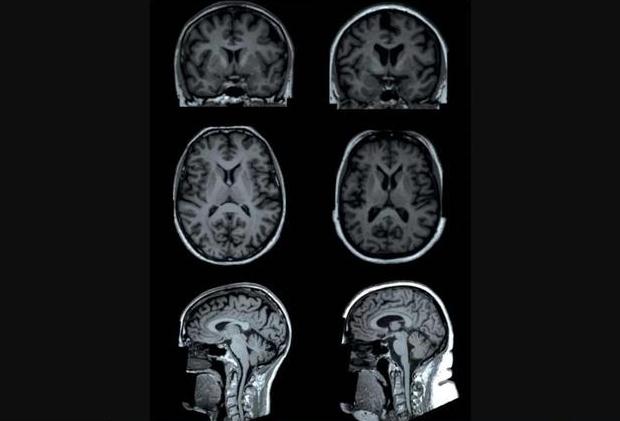

一項(xiàng)最新研究發(fā)現(xiàn),體脂越高,大腦某些區(qū)域容量就越小。上圖為研究中兩名測(cè)試者(年齡均為65歲的女性)的大腦核磁共振掃描。一名測(cè)試者(左側(cè)圖)體脂為13%,另一名測(cè)試者(右側(cè)圖)體脂為49%。核磁共振掃描顯示,與左圖測(cè)試者相比,右圖測(cè)試者大腦某些區(qū)域(“皮質(zhì)下區(qū)域”)灰質(zhì)容量較低。

新浪科技訊 北京時(shí)間4月28日消息,據(jù)國(guó)外媒體報(bào)道,肥胖與身體諸多有害影響有關(guān),目前,最新一項(xiàng)研究表明,肥胖還可能影響大腦結(jié)構(gòu),研究人員分析大腦掃描數(shù)據(jù),發(fā)現(xiàn)體脂越高,腦容量就越小。他們指出,尤其是身體脂肪過(guò)多與灰質(zhì)容量減少有關(guān),灰質(zhì)是包含神經(jīng)細(xì)胞的大腦組織,位于大腦中心區(qū)域。

4月23日發(fā)表在《放射學(xué)》雜志的一項(xiàng)研究表明,與女性相比,男性體脂與大腦容積之間的關(guān)聯(lián)性更密切。荷蘭萊頓大學(xué)醫(yī)學(xué)中心研究人員發(fā)現(xiàn),與體脂有關(guān)的大腦白質(zhì)——長(zhǎng)神經(jīng)纖維,可促使大腦各個(gè)區(qū)域進(jìn)行交流。

在這項(xiàng)最新研究中,研究人員分析了英國(guó)12087位測(cè)試者的信息數(shù)據(jù),他們平均年齡62歲。測(cè)試者接受核磁共振掃描,用于評(píng)估大腦灰質(zhì)和白質(zhì)結(jié)構(gòu),同時(shí),研究人員還使用一種叫做“生物電阻抗(bioelectrical impedance)”的方法測(cè)量了測(cè)試者體脂指數(shù),生物電阻抗是一種通過(guò)身體釋放小電流評(píng)估一個(gè)人體內(nèi)脂肪含量的方法。

研究人員發(fā)現(xiàn),體脂較高男性與灰質(zhì)整體容積較少有關(guān),同時(shí)與大腦中心某些較少容積灰質(zhì)區(qū)域有關(guān)。這涉及到丘腦、尾狀核、海馬體、蒼白核、殼核和伏核,其中一些區(qū)域參與大腦的獎(jiǎng)勵(lì)回路,另一些區(qū)域幫助調(diào)控身體運(yùn)動(dòng),對(duì)于女性群體而言,她們只存在體脂與蒼白核容量減少相關(guān)聯(lián)。對(duì)于男性和女性群體而言,與那些較低體脂者相比,較高體脂者與大腦白質(zhì)微觀結(jié)構(gòu)差異有關(guān)。